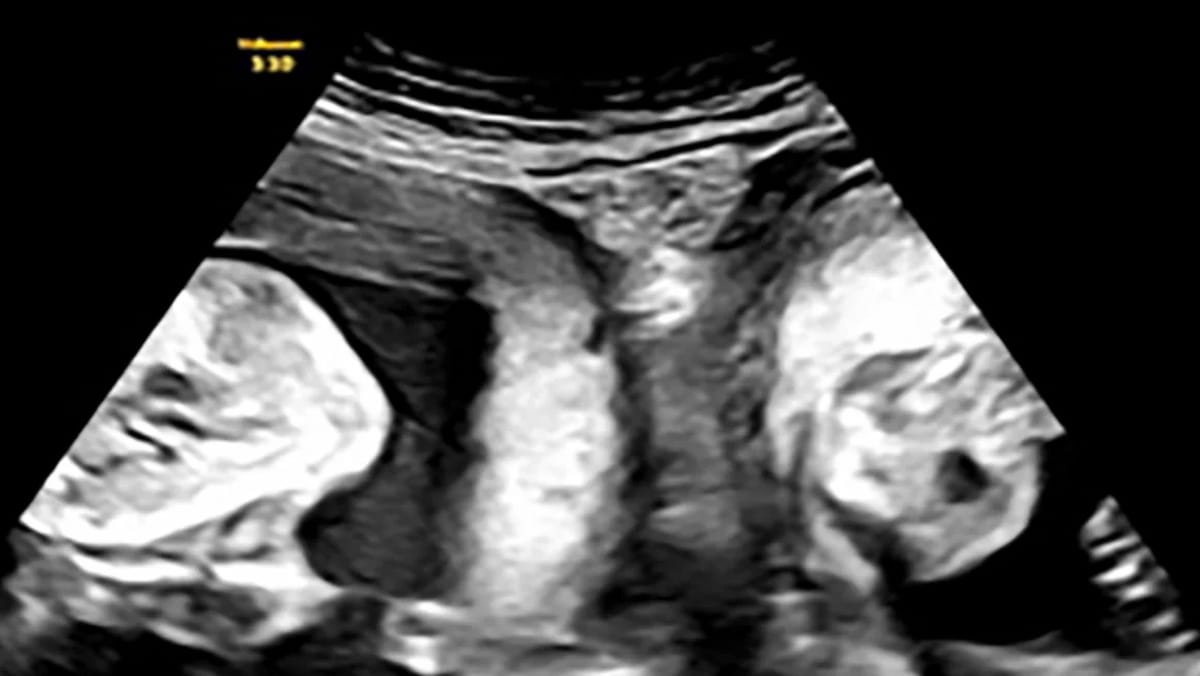

Ma a gennaio, Li è rimasta di nuovo incinta e ha scoperto durante un’ecografia precoce che non aspettava solo un bambino, ma due gemelli, uno in ogni utero.